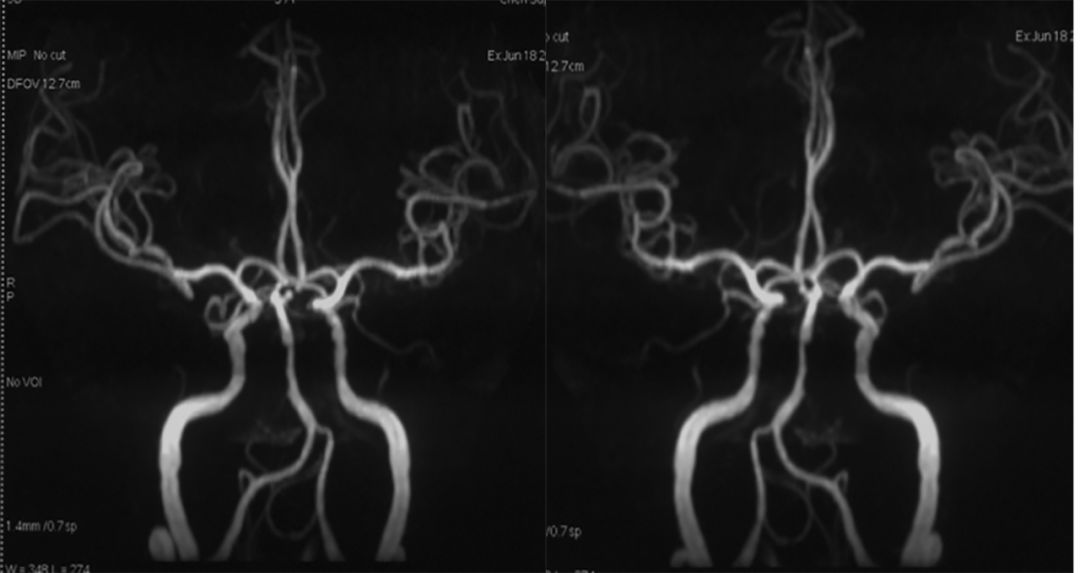

头MRA (2019-6-18 ,*** 人民医院):基底动脉末端动脉瘤,基底动脉中段狭窄(图2)。

图2

头颅CTA(2019- 6-18 ,*** 人民医院):基底动脉末端左侧小脑上动脉瘤,基底动脉中段狭窄(图3)。

图3

全脑血管造影(本院,2019-8-1 ):基底动脉顶端夹层或者开窗,左侧小脑上动脉瘤(图4)。

图4